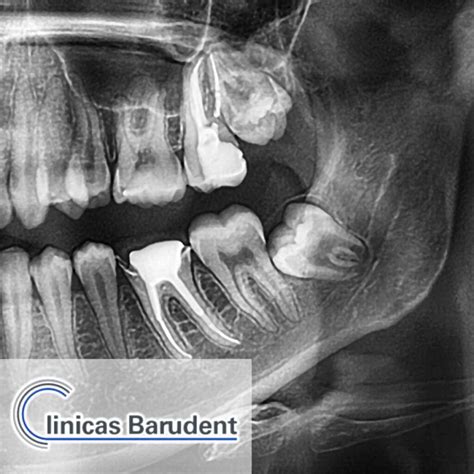

Radiografía mostrando muelas del juicio retenidas.